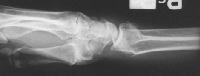

Clinical Example: Distraction plate fixation distal radius fracture

distal radius fracture